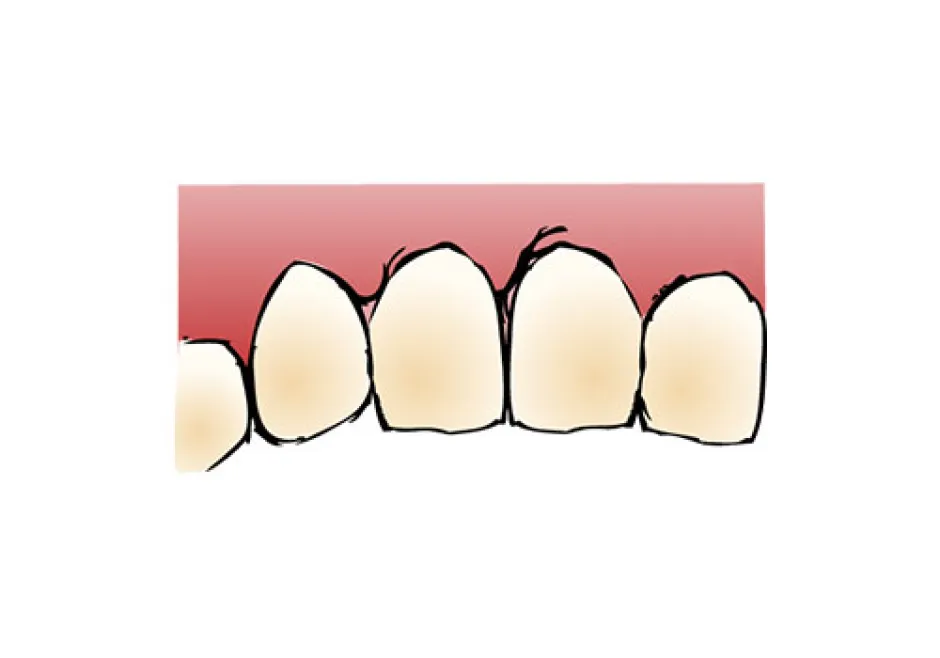

インプラント(implant)とは、“植え込む”という意味の英語です。インプラントの仕組みは、歯を失ってポッカリ穴が開いてしまった部分の歯龎骨へ穴を開け、インプラント体(フィクスチャー)と呼ばれる金属製の人工歯根(インプラント体)を埋め込み、その上に人工の歯を被せるしくみです。 歯龎の骨にしっかりとインプラント体を固定する事により、浮かない・ずれない・しっかりとした噛み心地を実現する事が出来ます。 人は永久歯を失うと、残念ながら二度と生え変わってきません。そのため、今までは『義歯(入れ歯)』『ブリッジ』などを用いて食事や会話 を取り戻すといった方法でしか、その部分を補う事はできませんでした。 しかし、『義歯(入れ歯)』だと固いものがうまく噛めない、発音がおかしい、また長く使っている間に合わなくなってガタガタする場合があります。 このように、歯を失ってお悩みの方にご提供することができる、最新歯科医療の治療方法『インプラント治療(人工歯根)」です。 歯を抜けたままにして放置しておくと、お口の中には様々な影響が出てきます。奥歯の下の歯が1本抜けた場合、まずこれまでその歯と噛み合っていた上の歯が下に伸びてきます。また、両隣の歯が抜けた歯の方向に倒れてきて、さらにはそこにプラークがたまりやすくなってしまいます。結果として、虫歯や歯周病などが誤発されることがあります。歯はかなり緬密に全体のバランスの中で成り立っているものなので、例え1本の欠損の場合でも、そのままにしておくことはお勧めできません。 機能的な影響 見た目上の影響 生活上の影響 取り外す入れ歯が嫌な方、取り外す入れ歯の清掃が面倒くさいと感じる方 入れ歯は食事のたびにお口から取って清掃しなくてはなりません。清掃が不十分だと歯周病の原因となります。お悩みの方は一度、ご相談下さい。 入れ歯が合わない方、何度も入れ歯をつくり直している方 入れ歯は歯肉を圧迫するので、歯肉がやせていきます。歯肉がやせると入れ歯との間に隙間ができ、密着しにくくなりお食事中などに外れる場合があります。 入れ歯で発音しにくい(話しにくい)方 入れ歯を使い始めてすぐは、発音のしづらさを感じます。人前で話す機会の多い方や英語を話す方は入れ歯により発音が悪くなります。特に、 楽器の演奏をされる方で前歯を失った場合には、インプラント治療が非常にお勧めです。 思いっきり笑ったり、歯を見せて話ができない方、入れ歯のバネが気になっている方 会話や食事の際など、お口をあけた時に入れ歯のバネが見えてしまう場合があります。入れ歯のバネが気になっている方は当院にご相談下さい。 口臭が気になる方 最近、口臭が原因で来院される患者様が増えています。実際に当院では口臭があると診断された患者様のほとんどの方が歯周病に侵されます。歯周病に侵され、残念ながら歯を失うことになった場合には、インプラント治療を勧められることがあります。 昔食べられていたものが噛めない方、左右片方でしかものが噛めない方 入れ歯は天然歯の1/3程度しか噛む力がありません。総入れ歯の場合は硬いものを噛むときに痛みを覚えます。昔の「歯」のようにしっかり噛 んで食事をしたいとお考えの方は一度、ご相談下さい。 自分の歯のように見た目をきれいにしたい方 インプラントは、天然歯とほとんどかわらない「機能性」「審美性」をもっています。自分の歯のように見た目を綺麗にしたいとお考えの方 は一度お問い合わせください。 健康な歯は、これからもできる限り残したい方 インプラント治療なら、隣の歯(まわりの健康な歯)を傷つけることなく欠損した歯だけを治療することが可能です。健康な歯を出来るだけ 残したいとお考えの方は当院までお問い合わせください。 旅行やスポーツを積極的に楽しみたい方 旅行先での美味しいものを存分に味わいたい、スポーツをする際、歯に力を入れたい、積極的に楽しみたいとお考えの方には、インプラント 治療がお勧めです。一度、当院にお問い合わせください。一つでもチェックした方はまず、当院へご相談下さい。 しっかりと噛める インプラントはあごの骨の中に埋め込まれ、しっかりと固定されますので、入れ歯とは違い、しっかりとした噛み心地が得られるのが大きな魅力です。しっかりと噛めるというのは、消化の面で良いのはもちろんですが、その他にも認知症の予防や、体の運動能力の向上にも役立つことがわかっており、若々しさを保つ上でも役立ちます。 見た目が自然 インプラントは人工歯根をあごの骨に埋め込み、その上に被せ物をする治療ですが、実際に表から見える部分というのは被せ物の部分だけです。被せ物は主に周囲の歯に似せたセラミックを入れますので、まるでご自分の歯のように見えます。 違和感がなく快適 インプラントの人工歯根は骨と結合して一体化し、まるで体の一部のような感じになります。一方、取り外し式の入れ歯の場合、歯茎の上に乗っているため、違和感に悩まされる方も少なくありません。 残った歯を長持ちさせてくれる インプラントは、単独で歯を立てられる治療法ですので、他の治療法と違い、周囲の歯にダメージを与えることがありません。例えばブリッジの場合、失った歯の両隣の歯をたくさん削って被せなければなりませんし、入れ歯の場合だと、残っている歯に金具をかけて入れ歯を支えなければなりません。このような周囲の歯へのダメージが徐々に歯を弱らせてしまうことにつながっていき、最終的には歯の寿命を短くしてしまいます。単独で歯をおぎなうことのできるインプラントは、歯を全体的に健康に保ってくれる治療法だと言えるでしょう。 お手入れが楽 インプラントは、基本的にご自分の歯を磨くようにお手入れをします。一方、入れ歯の場合は取り外して入れ歯とご自分の歯を別々に磨く必要がありますし、ブリッジの場合には、つなぎの部分などの形が複雑で、隅々まで磨くのが大変です。 あごの骨がやせにくい インプラントとあごの骨はしっかりと結合していますので、噛んだ刺激は直接骨に伝わります。あごの骨というのは噛む刺激を受けないとだんだんやせてしまいます。そのため、入れ歯やブリッジの場合には徐々に骨がやせていきます。インプラントの場合には常に噛む刺激が伝わるため、骨の高さが維持されてお顔の張りも保たれることになり、若々しい見た目を維持することができます。 保険適用にならない 通常、インプラントは保険が適用されません。そのため、治療費は100%自己負担となりますので高額になってしまいます。 手術を受けなければならない インプラントは人工歯根をあごの骨に埋める手術が必要です。手術の侵襲の程度は抜歯程度のものが多いですが、やはり外科的な処置が必要になります。 治療期間が長くかかる インプラントは他の治療法に比べて治療期間が長くかかります。それはインプラントがあごの骨と結合するまでじっくりと待たなければならないためです。通常、下あごの場合3ヶ月程度、上あごの場合6ヶ月程度ほど治療期間がかかりますが、骨が少ない場合には骨を作る治療が必要となりますので、さらに数ヶ月かかることもあります。 全身状態、骨の状態などによっては治療不可 糖尿病や高血圧がしっかりとコントロールされていない場合など、全身状態によっては手術が行えない場合があります。また、インプラントを埋める部分の骨の状態が良くない場合には行えない場合があります。 メンテナンスを怠ると抜け落ちることがある メンテナンスは、どの治療法にとっても長く持たせるためには必要不可欠ですが、インプラントの場合、毎日のお手入れや、歯科医院での定期的なメンテナンスを怠ると細菌感染を起こし、ご自分の歯と同様、抜け落ちてしまうことがあります。特にタバコを吸う場合、インプラント周囲の組織が感染を起こしやすくなるため、より注意が必要です。 失った部分にインプラントを1本埋入します。 従来は部分的な入れ歯を用いて治療を行っていましたが、インプラントを何本か用いて治療を行います。入れ歯を固定するための金属のバネによる違和感がなくなります。 従来の総入れ歯ではなくインプラントを用いて治療します。この方法なら食物が入れ歯と歯茎の間にはさまったり、入れ歯が合わなくなるようなことはありません。 LMGでは実際に当院で行ったインプラント手術の症例を公開しております。歯を失ってしまった方や、歯周病等で歯を残すことが困難と診断された方は当院でのインプラント治療なら綺麗で咬みやすい口腔内を取り戻すことができるかもしれません。ぜひチェックしてみてください。 あらゆる治療に言えることですが、インプラント治療は思い立ってすぐに取り掛かれる治療ではありません。インプラントはあごの骨を削る治療も必要ですので、安全に治療を進めていく上でも、治療を開始するにあたって十分な検査や前準備が必要となります。 インプラントはあごの骨を削る治療も必要ですので、安全に治療を進めていく上でも、治療を開始するにあたって十分な検査や前準備が必要となります。 インプラント治療についてあまりよく知らない、という方も多いと思います。 そのため、患者様がすでにインプラントをご希望されている場合でも、まずは十分なカウンセリングを行ない、ご理解を深めていただいた上で治療を進 めていくことになります。 患者様の歯のお悩み、ご希望をお聞きした上で、インプラント治療についての 説明を行います。インプラント治療の治療の進め方、どのような手術になるの か、リスク、期間、費用、またインプラント治療のメリットだけでなくデメ リットに関しても詳しくお話しいたします。 院では、患者様に十分にインプラント治療をご理解いただき、ご納得いただ いた上でインプラント治療を開始するようにしています。不安な点、疑問な点 などはどんなことでもためらわずにお話しください。 もちろんインプラント以外の可能な治療法に関しても、すべてメリット、デメ リットも含めてご説明し、患者様ご自身に合った方法をお選びいただきます。 インプラントを行うためには、お口の状態の検査をしっかりと行う必要があります。それは他の治療に関しても同じことが言えるのですが、インプラントの 場合には特に、あごの骨の適切な位置にインプラントを狂いなく埋め込む必要があります。 それゆえ、安全に手術を行うためには、通常のレントゲンだけでなく、CT撮影も行なった上で、骨の状態や神経や血管の位置まで詳しく診査を行う必要があります。また、インプラントをベストな状態で行うためにも、お口の健康状態、かみ合わせの状態などもチェックしておきます。 検査結果をもとに、治療計画を綿密に立てていきます。患者様にベストと思われる治療計画をわかりやすくご説明し、ご納得いただければ治療開始となりま す。ただし、場合によってはすぐにインプラント治療が開始できない場合もあります。 たとえば大きな虫歯や、重度の歯周病がある場合、体の健康状態に問題がある場合などです。このような場合には、まずインプラントが健全な状態で行えるよう、問題点を解決してからインプラント治療に移行していきます。 手術の大まかな流れを説明します。手術の方法やインプラントの本数によって手術の計画は変更となります。 01 埋入手術 麻酔を行なった後、インプラントをあごの骨に埋め込んでいきます。多くの場合、抜歯程度の手術になりますので、通常の歯科の麻酔で問題なく手術が行えます。約3〜6ヶ月ほどの治癒期間を待ちます。 02 頭出し手術 インプラント手術を二回法で行なった場合に行われる簡単な手術です。歯茎で覆われていたインプラントの上部を露出させ、1〜2週間以上経ってから被せ物の型取りを行います。 03 被せ物の装着 出来上がった被せ物を装着します。 04 メインテナンス 長期的に良い状態でインプラントを保ち続けるために、定期的に通っていただきメインテナンスをお受けください。 インプラントは生体に埋め込む治療ですので、治癒期間などが必要となり、どうしても他の治療に比べて期間がかかってしまいます。そのため、インプラント手術を開始してから被せ物が最終的に入るまでに、3〜6ヶ月くらいはかかります。 この期間は骨の状態や手術の方法によって変わってきます。また、インプラント治療を開始する前に虫歯や歯周病の治療が必要な場合にはさらに期間がかかる場合もあります。 LMGでは実際に当院で行ったインプラント手術の症例を公開しております。歯を失ってしまった方や、歯周病等で歯を残すことが困難と診断された方は当院でのインプラント治療なら綺麗で咬みやすい口腔内を取り戻すことができるかもしれません。ぜひチェックしてみてください。しっかりとした噛み心地を実現する治療

当院のインプラント治療に対するこだわり・コンセプトをお伝えし、患者さまに安心して治療を受けていただきたいと思います。 歯を失うに至った経緯と改善できることをまず理解していきましょう。なぜ歯を失うまで至ったのか、それに対して患者様が改善できることは何なのかを私たちとともに理解していただきます。 インプラントはあくまで歯の代用品です。もともと歯を失った根本的原因が何であるかしっかり把握しておかなければインプラントを入れたとしてもまた同じこと(インプラントを失う)を繰り返す可能性だってあるのです。 ですから、ライフメディカル総合歯科クリニック八潮ではなぜ歯を失うまで至ったのか、それに対して患者様が改善できることはなんなのかを私たちとともに理解していただきます。そして改善が実践できた次のステップにインプラント治療があると考えています。 それをしなければ雨漏りで腐った柱の修理に雨漏りを直さず柱だけ取り替えるようなものです。ましてやインプラントは異物です。感染にも本来の自分の歯以上に気を配る必要性があります。 一般的に歯の治療と考えられている、詰める、かぶせる、神経を取る、入歯にするなどの行為は困った現状、つまり症状に対してなされる行為であり、「対症療法」と言われています。しかし虫歯や歯周病の原因となる細菌が取り除かれているわけではありません。現状から抜け出ることはできないのです。 通常インプラント治療を選択するケースでは歯周病が原因で歯を失ったケースが多いです。インプラントは対症療法に過ぎません。根本原因である歯周病の治療を行わずに治療は完了しません。 ライフメディカル総合歯科クリニック八潮では根本原因を除去し対処を行い、今後再発しないように万全の態勢を整えて、インプラント治療を開始します。インプラント治療の成功につながる大切なベース作りを入念に行います。インプラント治療のこだわり